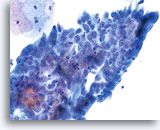

Konventioneller Pap-Abstrich

Adenokarzinom

ThinPrep® Pap Test

Adenokarzinom